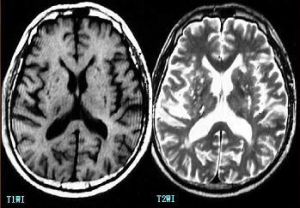

腦腔梗病變範圍一般為2-20毫米,其中以2-4毫米者最為多見。臨床上腦腔梗患者多無明顯症狀,約有3/4的患者無病灶性神經損害症狀,或僅有輕微注意力不集中、記憶力下降、輕度頭痛頭昏、眩暈、反應遲鈍等症狀。該病的診斷主要為CT或MRI檢查。而多發性的腦腔梗,可影響腦功能,導致智力進行性衰退,最後導致腦血管性痴呆。